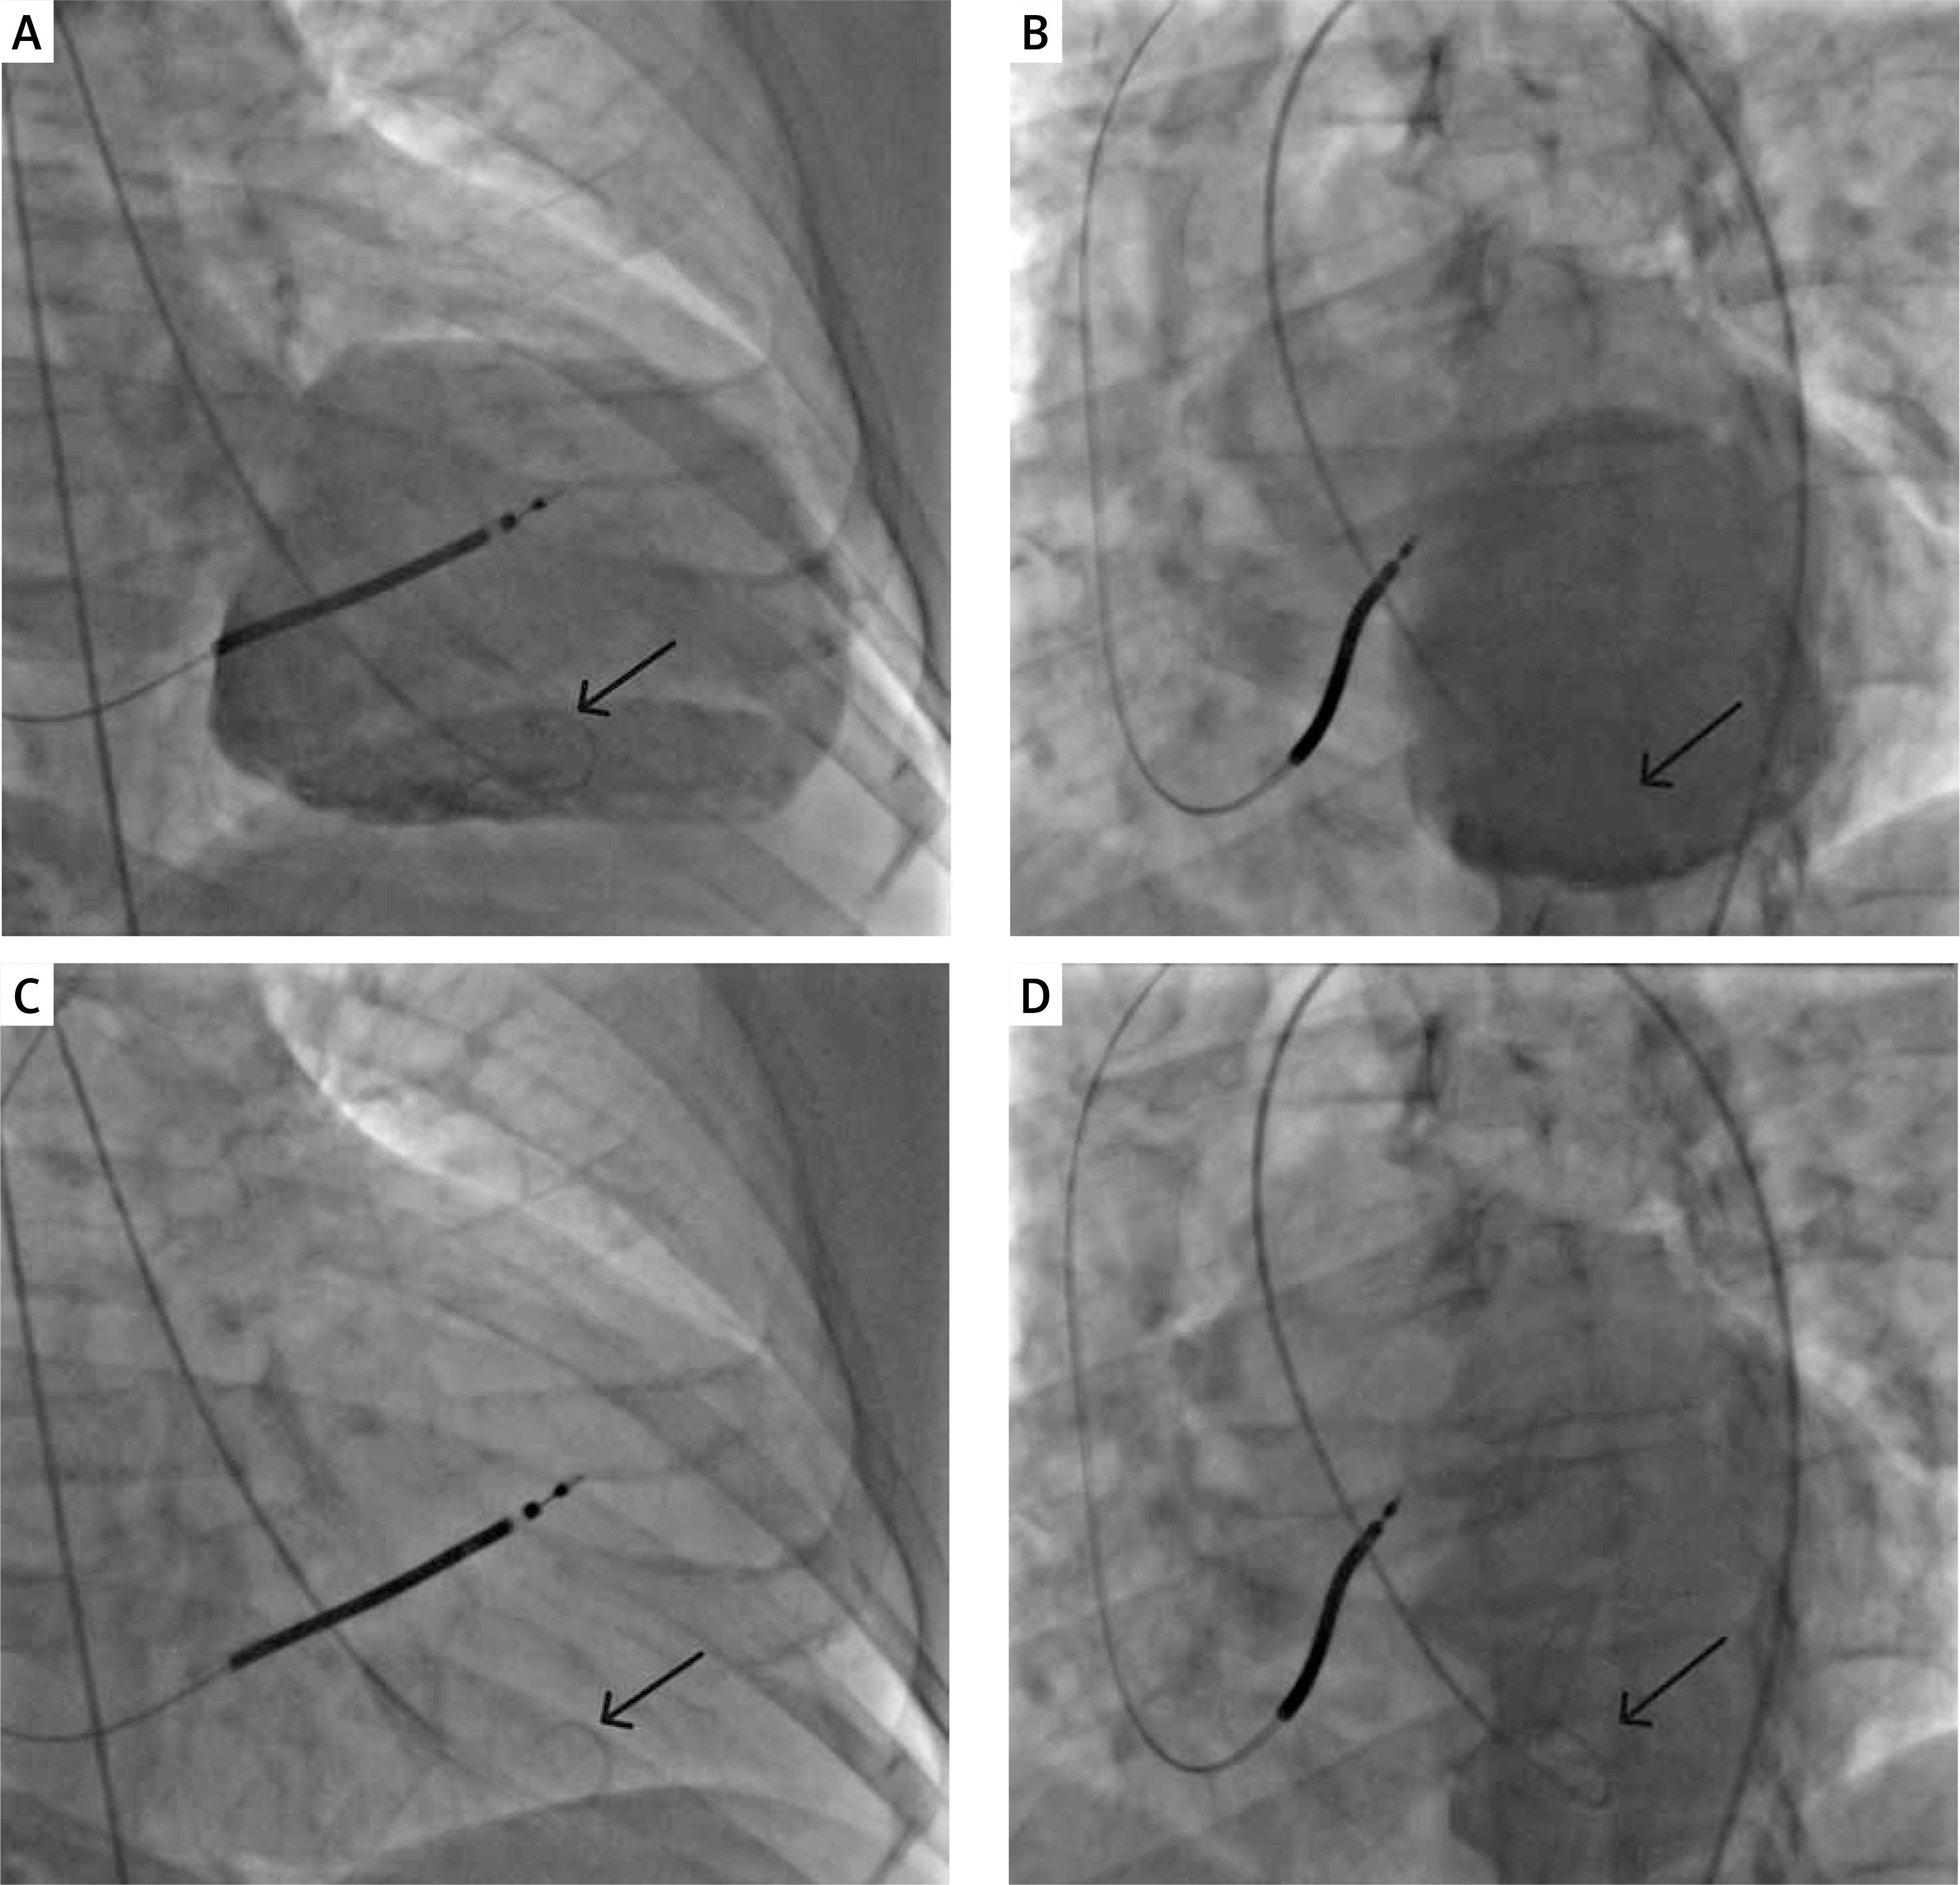

Figure 2

Example of a ‘sham procedure’. A, B – Ventriculography (A – antero-posterior (AP) and B – left anterior oblique (LAO) view); C, D – Sham procedure, pigtail catheter positioned in the corresponding projections (C – AP, D – LAO view); low volume saline injections (n = 15-20) mimicking CSCs delivery